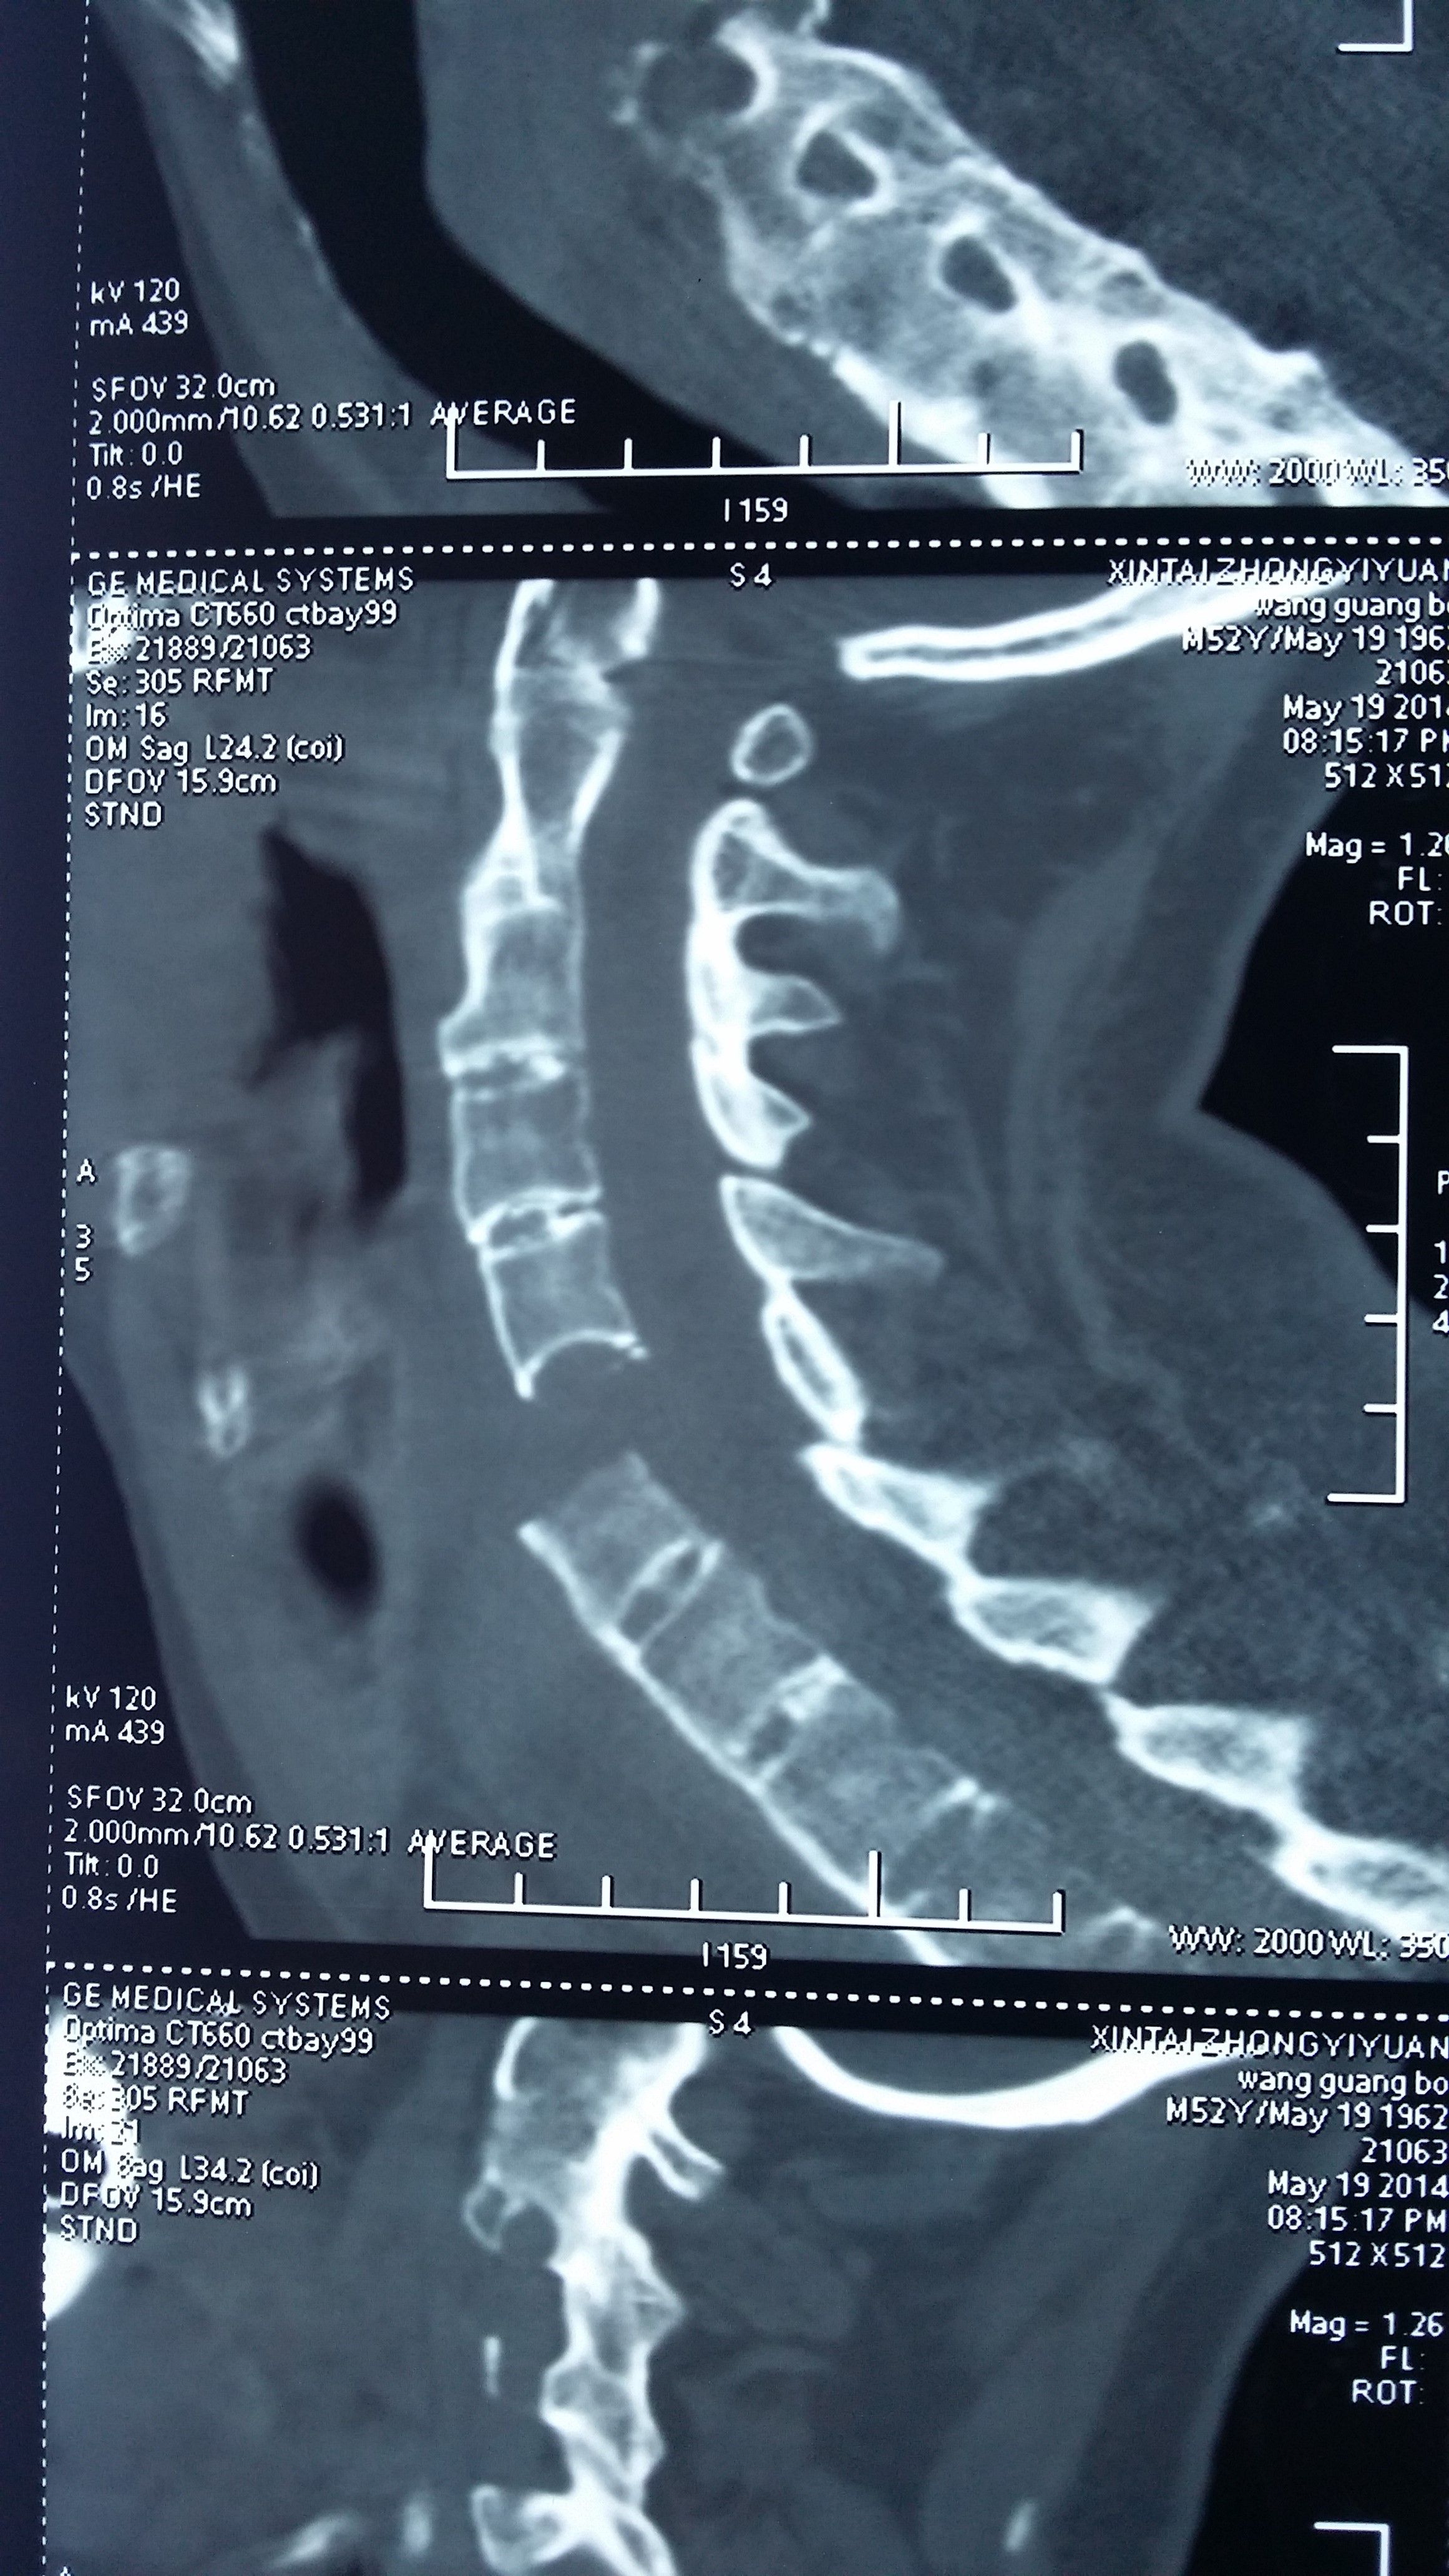

病人王某,男性,51岁,因“颈背部外伤后疼痛、双手麻木3小时”入院。系摩托车撞伤,先后咨询我市多家医院,均不敢收治。入院时病人双手中指、食指麻木,双上肢肌力Ⅲ级,双下肢肌力Ⅳ级。CT检查显示:颈5、6椎体及附件爆裂骨折、脱位并椎管狭窄,强直性脊柱炎。颈椎磁共振检查显示:颈髓受压,髓内未见明显高信号。我院即刻给予颈托外固定,完善术前检查,给予颈椎前路植骨融合内固定术,术后恢复好,术后影像复查显示骨折解剖复位,病人无不适感觉,行走同受伤前,20天后痊愈出院。

强直性脊柱炎的病理变化包括脊柱骨性强直、椎体骨质疏松等,导致脊柱骨脆性增加,较常人更容易发生骨折,该类骨折的损伤机制多属过伸伤,颈胸腰段均可发生,可导致四肢瘫、截瘫,致残率极高,死亡率高,对病人、家庭是巨大的灾难。高颈椎椎体骨折治疗风险高,技术难度大,一般医疗单位不愿意承担如此高风险的挑战。对该病人计划采用前后路联合固定治疗,因强直性脊柱炎所致的胸椎后突畸形显著,手术体位摆放困难,仅进行了前路植骨融合手术,术后强化颈托固定,以利骨性愈合。目前病人手术后三个月,复查CT显示:骨折解剖复位,有骨痂生长,无不良感觉,行走自如,与受伤前相比没有不适,劳动能力完全恢复,实现了回归社会的最好要求。

图一:伤后即刻CT片